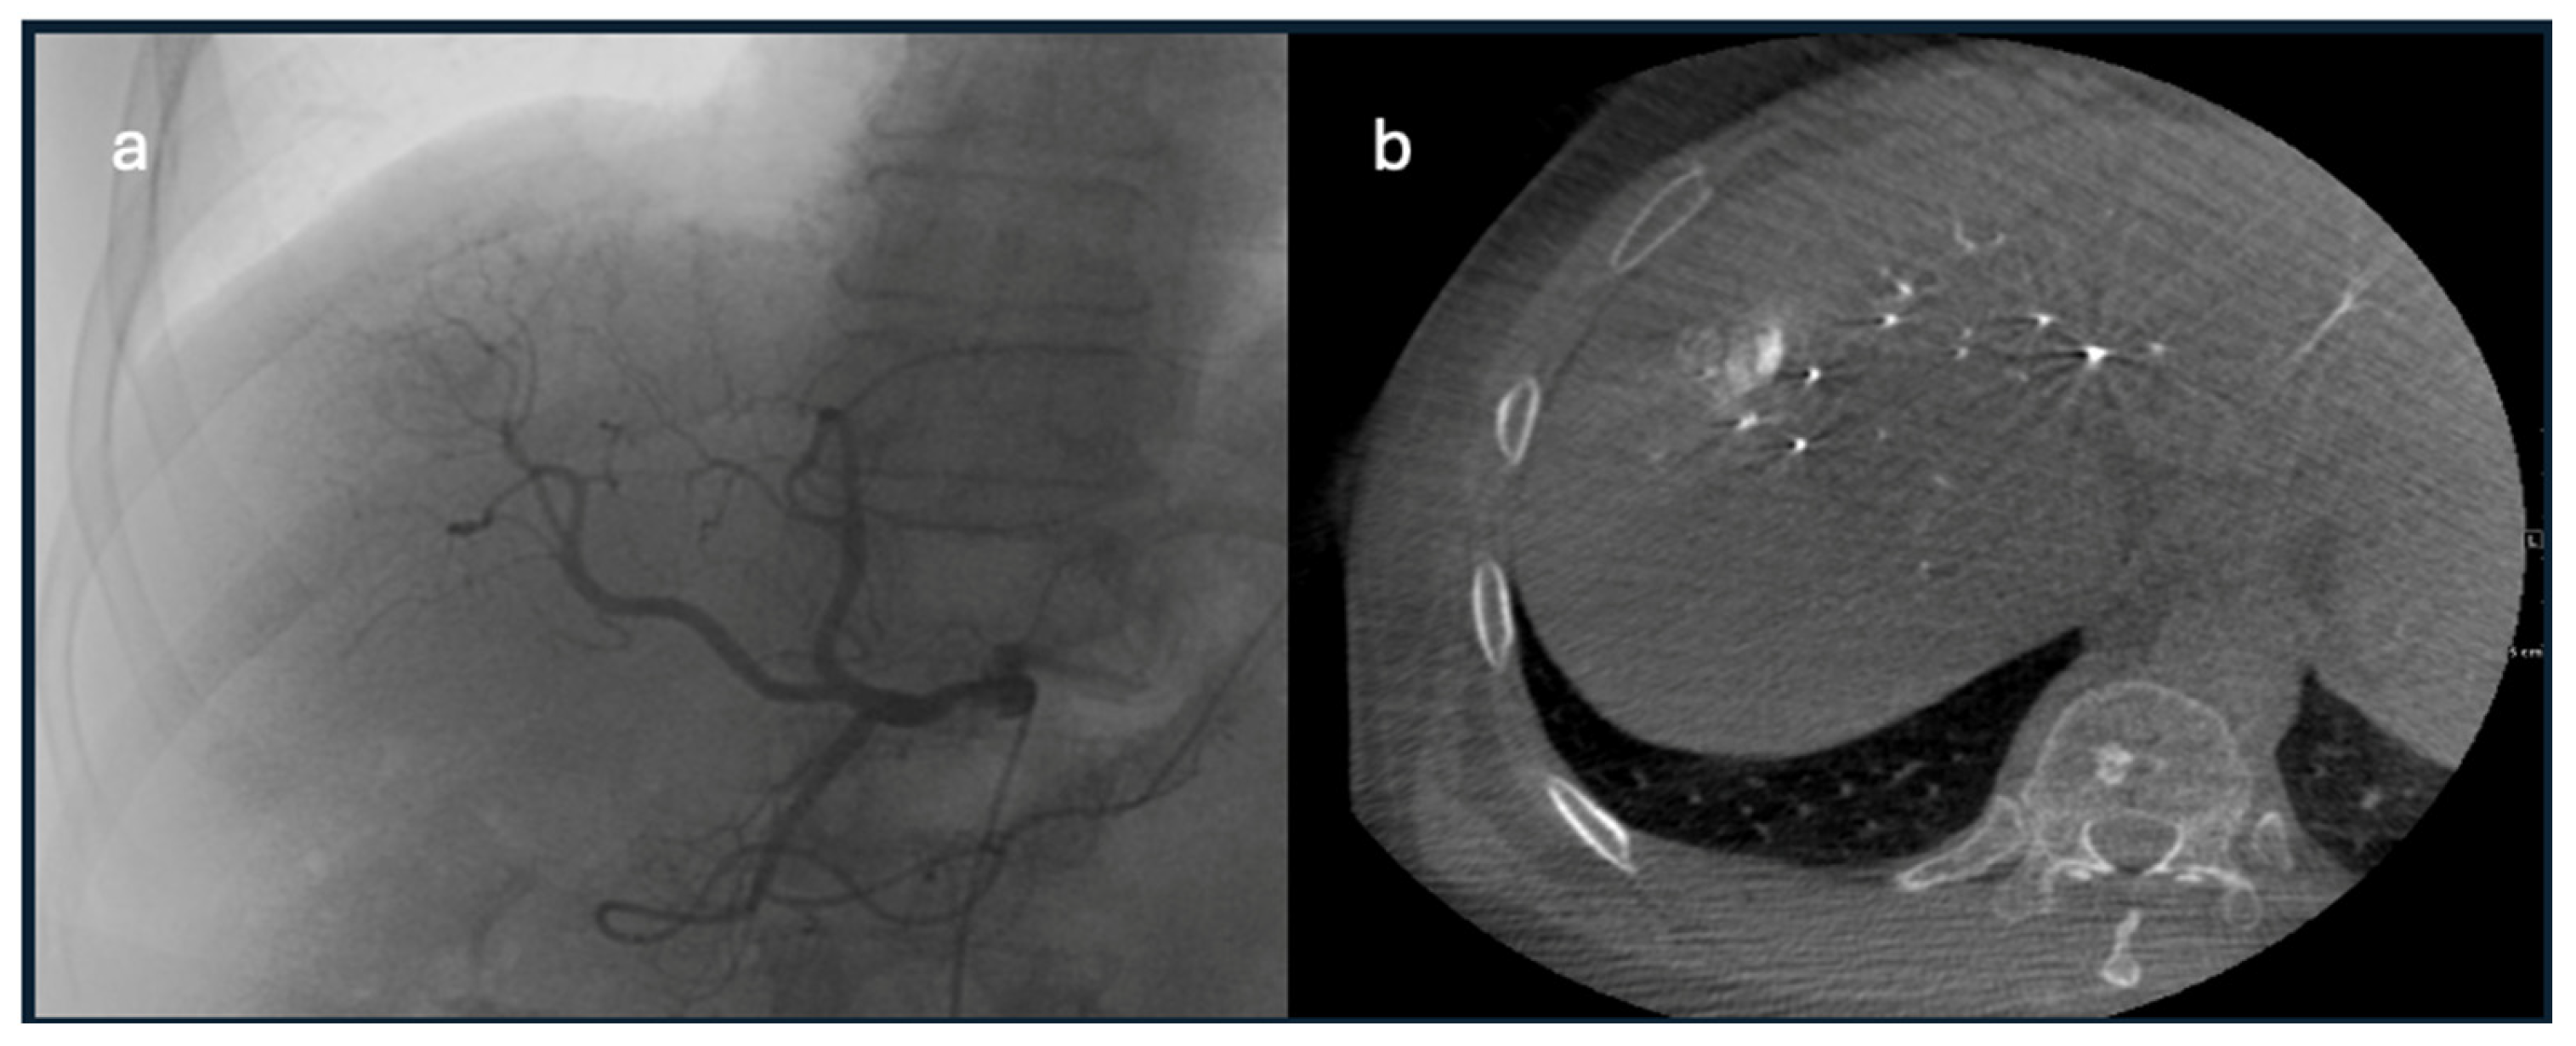

- Accessory extra-mesenteric arteries: Tumors that are located anteriorly at liver dome segments 2, 4A, and 8 may receive accessory supply from the internal mammary artery, a branch of the right subclavian artery. However, HCC located posteriorly at liver dome segments 8, 7, and 2 and the caudate may receive accessory supply from the inferior phrenic artery, a branch of the celiac trunk or directly originating from the abdominal aorta [64]. A subcapsular tumor near the ribs may receive accessory supply from intercostal arteries, as shown in Figure 5 [65].